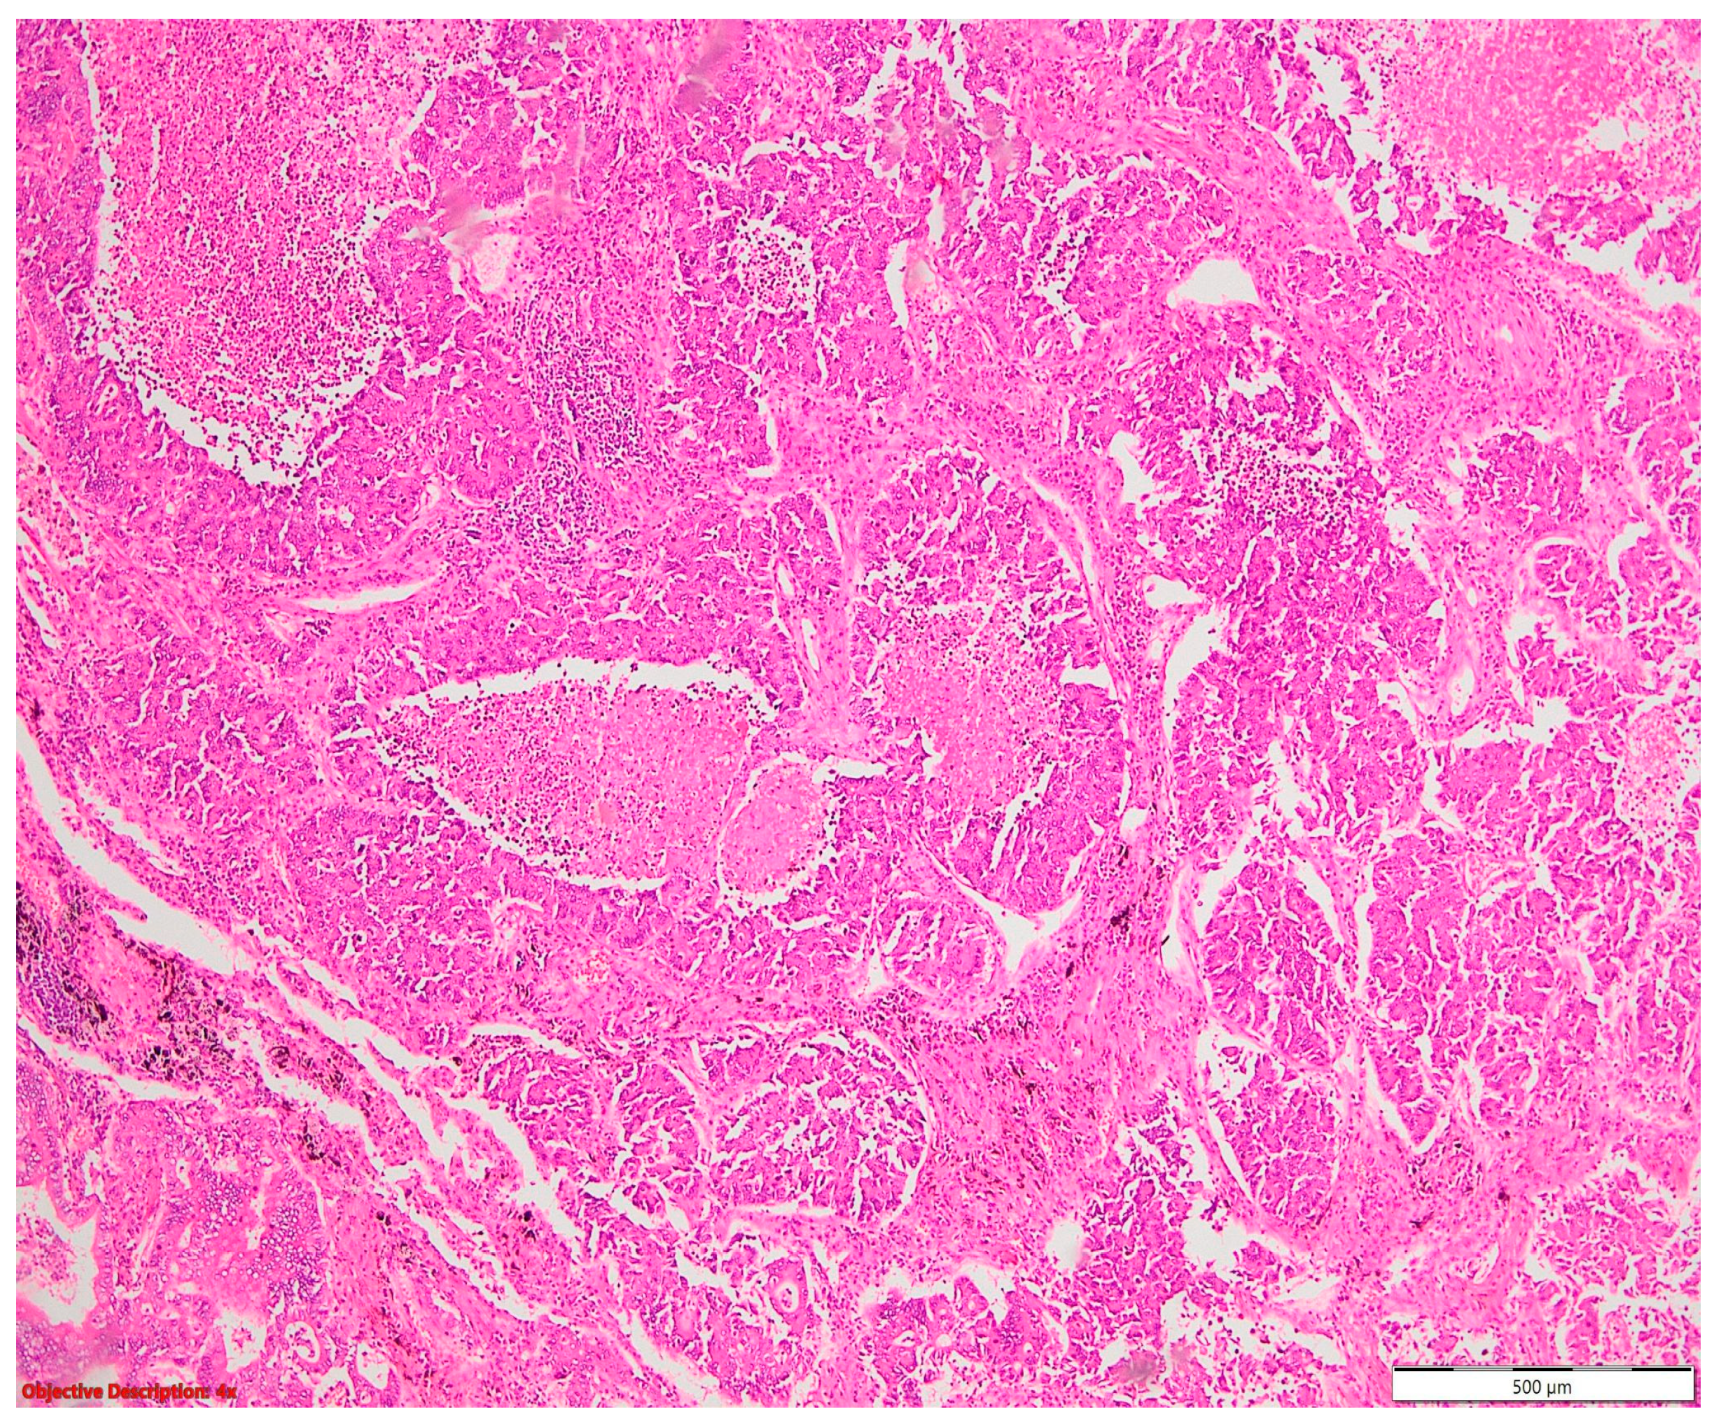

Figure 7. Lung squamous cell carcinoma (large polygonal cells with infiltrative pattern of growth; keratinization is evident →); HE, 40×.

Two of the specimens with fibronodular lesions were associated with multiple NSCLC tumors of different histopathological subtypes: one case presented with adenocarcinoma (one tumor—Figure 6) and a squamous cell tumor (one tumor—Figure 7) and another case presented with adenocarcinoma (one tumor) and large-cell neuroendocrine tumors (two tumors—Figure 8).